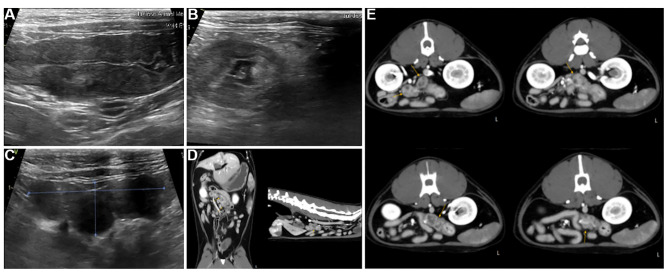

Case report: A 7-year-old castrated male domestic shorthair cat (4.1 kg) presented with anorexia and vomiting. Blood tests showed an albumin:globulin ratio of 0.5, a mild elevation in aspartate aminotransferase, mild leukocytosis, and a severe elevation of feline serum amyloid A. The abdominal ultrasound and computed tomography imaging showed a mass in the transverse colon and surrounding mesenteric lymph nodes. The mass was observed to be relatively well vascularized, with areas of low-density uneven necrosis. Histological examination revealed severe pyogranulomatous inflammation with macrophages, neutrophils, and lymphocytes predominantly present in both the affected colon and lymphoid tissues. Immunohistochemistry for feline infectious peritonitis (FIP) virus antigen of the lesion showed a strong positive result, confirming limited and localized lesion induction by FIP virus infection. The cat received GS-441524 for 12 weeks, resulting in clinical improvement, lesion resolution, and normalized lab results. RT-PCR and antibody tests were negative post-treatment.